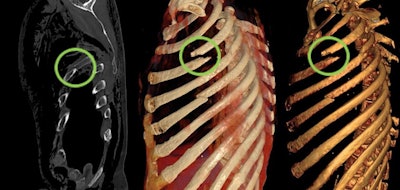

Between February 2016 and March 2019, Böven and her colleagues analyzed 112 fractures and injuries from 33 human cadavers (8 women, 25 men, with a mean age of 54 ± 18 years, range 31-92 years) that underwent whole-body postmortem CT after traumatic death. They reconstructed pathologies with CR and VR techniques, and classified fractures according to their dislocation.

Two forensic pathologists evaluated images according to their expressiveness and judicial relevance, and they decided whether CR reconstructions were suitable for judicial reviews. Two radiologists determined the detection rate of pathologies, and a traumatic cause of death was included.

CR was more expressive than VR for all three trauma categories (p < 0.01). Also, CR was more expressive than conventional CT when used for fractures with dislocation (p < 0.001), injuries of the ventral body surface (p < 0.001), and demonstration of foreign bodies (p = 0.033). CR and VR became more expressive with a higher grade of fracture dislocation (p < 0.001). In total, 20% of all pathologies in the CR and VR reconstructions were not detectable by radiologists.

"CT showed the same evaluation for expressiveness given by forensic pathologists in every grade of dislocation, whereas a strong correlation between grade of dislocation for fractures and CR expressiveness was found, as well as for VR reconstruction images," the authors wrote. "Reconstructions of fractures with major dislocation were declared useful for forensic reports in 84% of the cases."

"Due to the findings of our study, the use of CR for judicial reviews but also for other clinical demonstrations became the method of choice in our institute," Böven pointed out. "We also use CR reconstructions to demonstrate soft tissue injuries like stab wounds and penetration of foreign bodies more often than before."